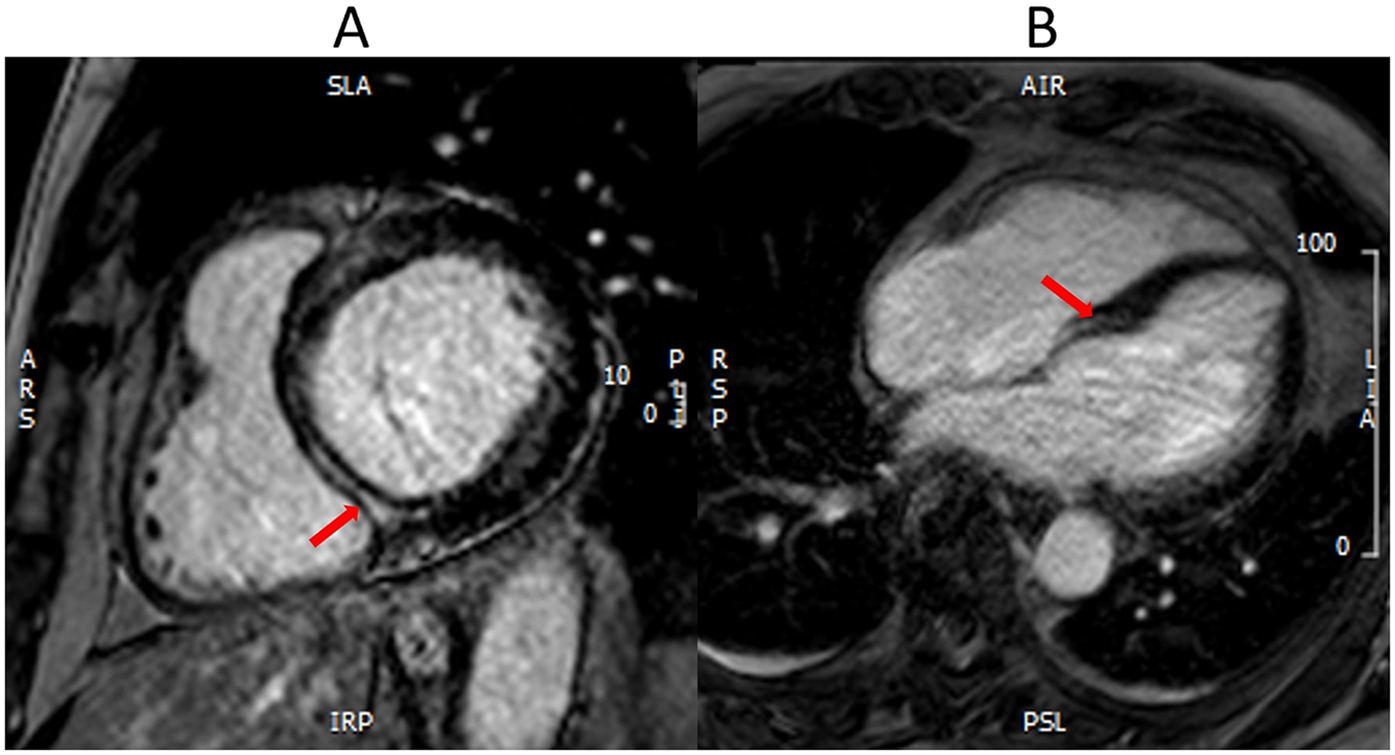

CMR is being increasingly utilized as a well-validated technique for the assessment of scar and fibrosis (33). CMR utilizes late gadolinium enhancement (LGE), native T1 mapping, and post contrast T1 mapping for extracellular volume fraction (ECV) to assess scar burden, diffuse fibrosis, and extracellular space (Figures 1, 2).

Myocardial fibrosis with CMR. CMR LGE demonstrates a white stripe (red arrows) in the mid-wall of basal inferoseptum in the short axis view (A) and four-chamber view (B). This mid-wall fibrosis is consistent with the non-ischemic scar pattern seen in non-ischemic cardiomyopathy.